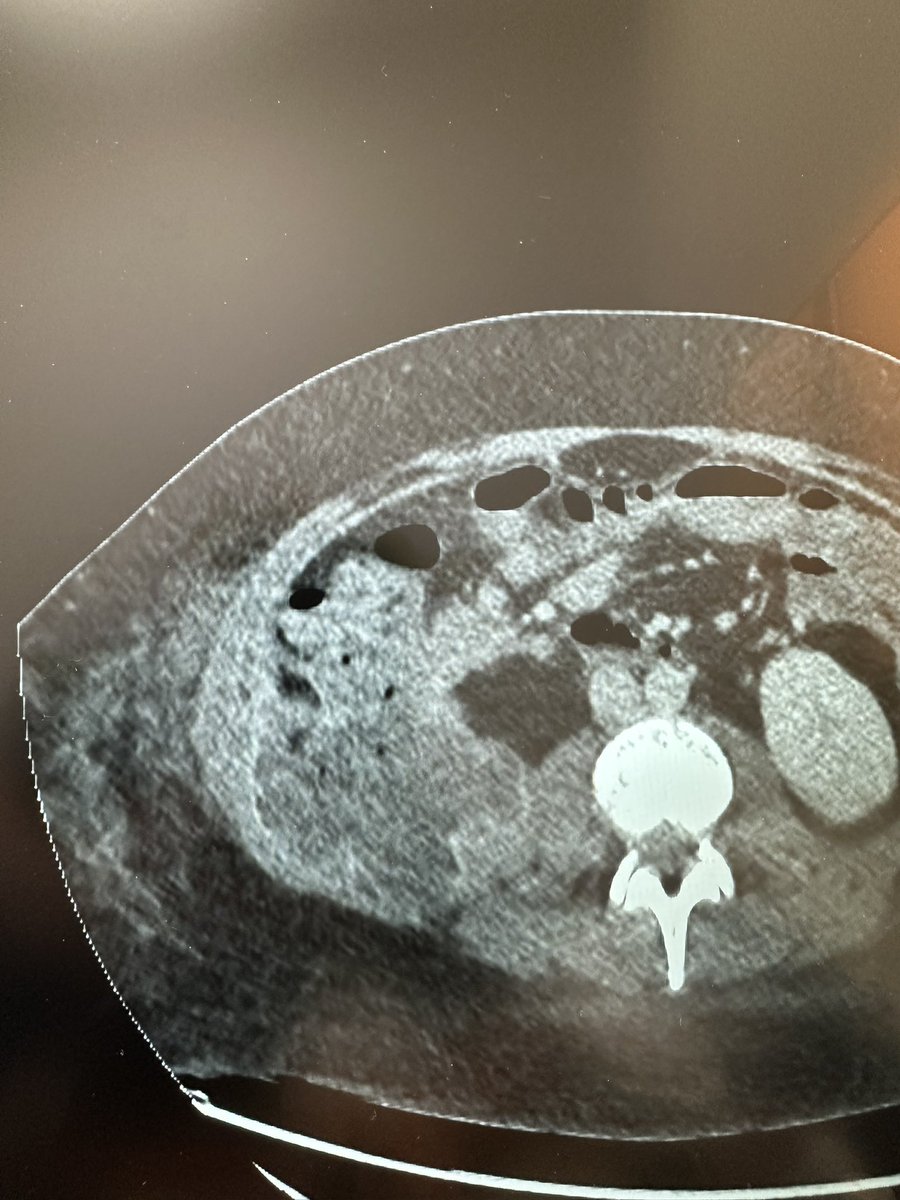

لولا وجود الندبة الجراحية لما صدّقت. مريض سبق وأن عمل عملية دوالي خصية مجهرية (مايكروسكوب) وبالطبع لم يتم علاجها بالشكل الصحيح. الأشعة التداخلية وضحت دوالي مهولة من ناحية العدد والحجم… لماذا يتعرض المريض للعملية بمخاطرها (ضمور صامت بنسبة ١ من كل ١٤٠ مريض أو قيلة مزمنة بنسبة ١-٢

لا يمكن للجراحة (بكل انواعها) ربط كل دوالي الخصية بأمان. هنا مثال لمريض عمل عملية "منظار" لربط الوريد الخصوي من الظهر (لمحاكاة طريقة القسطرة) وبالطبع يتضح وجود أوردة لم يتم ربطها ولذلك لم يتم حل المشكلة. المصيبة أن هذه العملية بالذات معروفة بنسبة عالية من حدوث المضاعفات مثل